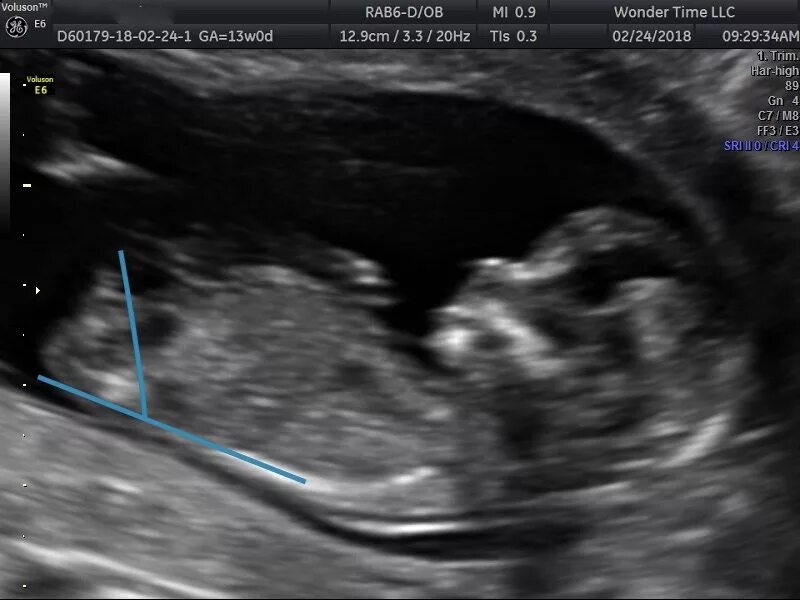

На каком скрининге узнать пол